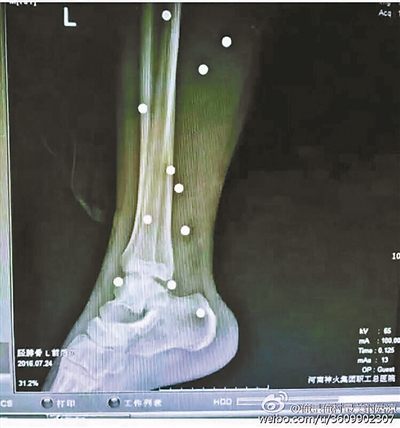

傷者體內(nèi)取出的鋼珠

爆炸導(dǎo)致鋼珠遍布傷者身體各處

黃明的伯伯對北青報(bào)記者表示,由于黃明直接踩到了爆炸物,所以傷情最為嚴(yán)重,“他的腿被炸斷,身體內(nèi)被炸進(jìn)了40多顆鋼珠。手術(shù)后已經(jīng)從體內(nèi)取出29顆鋼珠,還有十多顆鋼珠沒有取出來。”根據(jù)黃明的入院記錄,他全身有多處爆炸傷,且全身多處異物存留。

爆炸發(fā)生時(shí),陳浩的位置與黃明靠得很近,因此也受傷較重。他告訴北青報(bào)記者,經(jīng)過10多個(gè)小時(shí)的手術(shù)后,醫(yī)生從他身體里取出了12顆鋼珠。目前,他和黃明兩人經(jīng)過手術(shù)后,已從重癥監(jiān)護(hù)室轉(zhuǎn)至普通病房。其余三人中,陳剛的臀部受傷,當(dāng)天晚上在醫(yī)院清理完傷口后便回了家,而同行的兩名女生身上有一些擦傷。